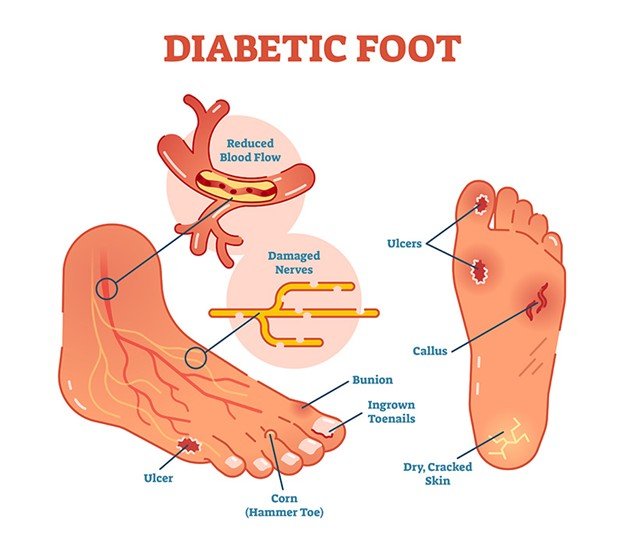

One of the most severe diabetes complications, diabetic foot ulcers. It usually result in infection, hospitalization, and even amputation without appropriate treatment. Treatment is critical to ensure healing, prevent complications, and enhance life quality. This article examines the various management methods of diabetic foot ulcers and the results that patients can attain when managed well.

Understanding Diabetic Foot Ulcers

DFUs are open wounds or ulcers that usually develop on the lower part of the foot in diabetic patients. They ocurr due to diabetes complications like peripheral neuropathy (nerve damage), lack of circulation (ischemia), and infection. These ulcers are severe as they raise the susceptibility of infections. It may result in hospitalization, amputation and severe health complication without treatment.